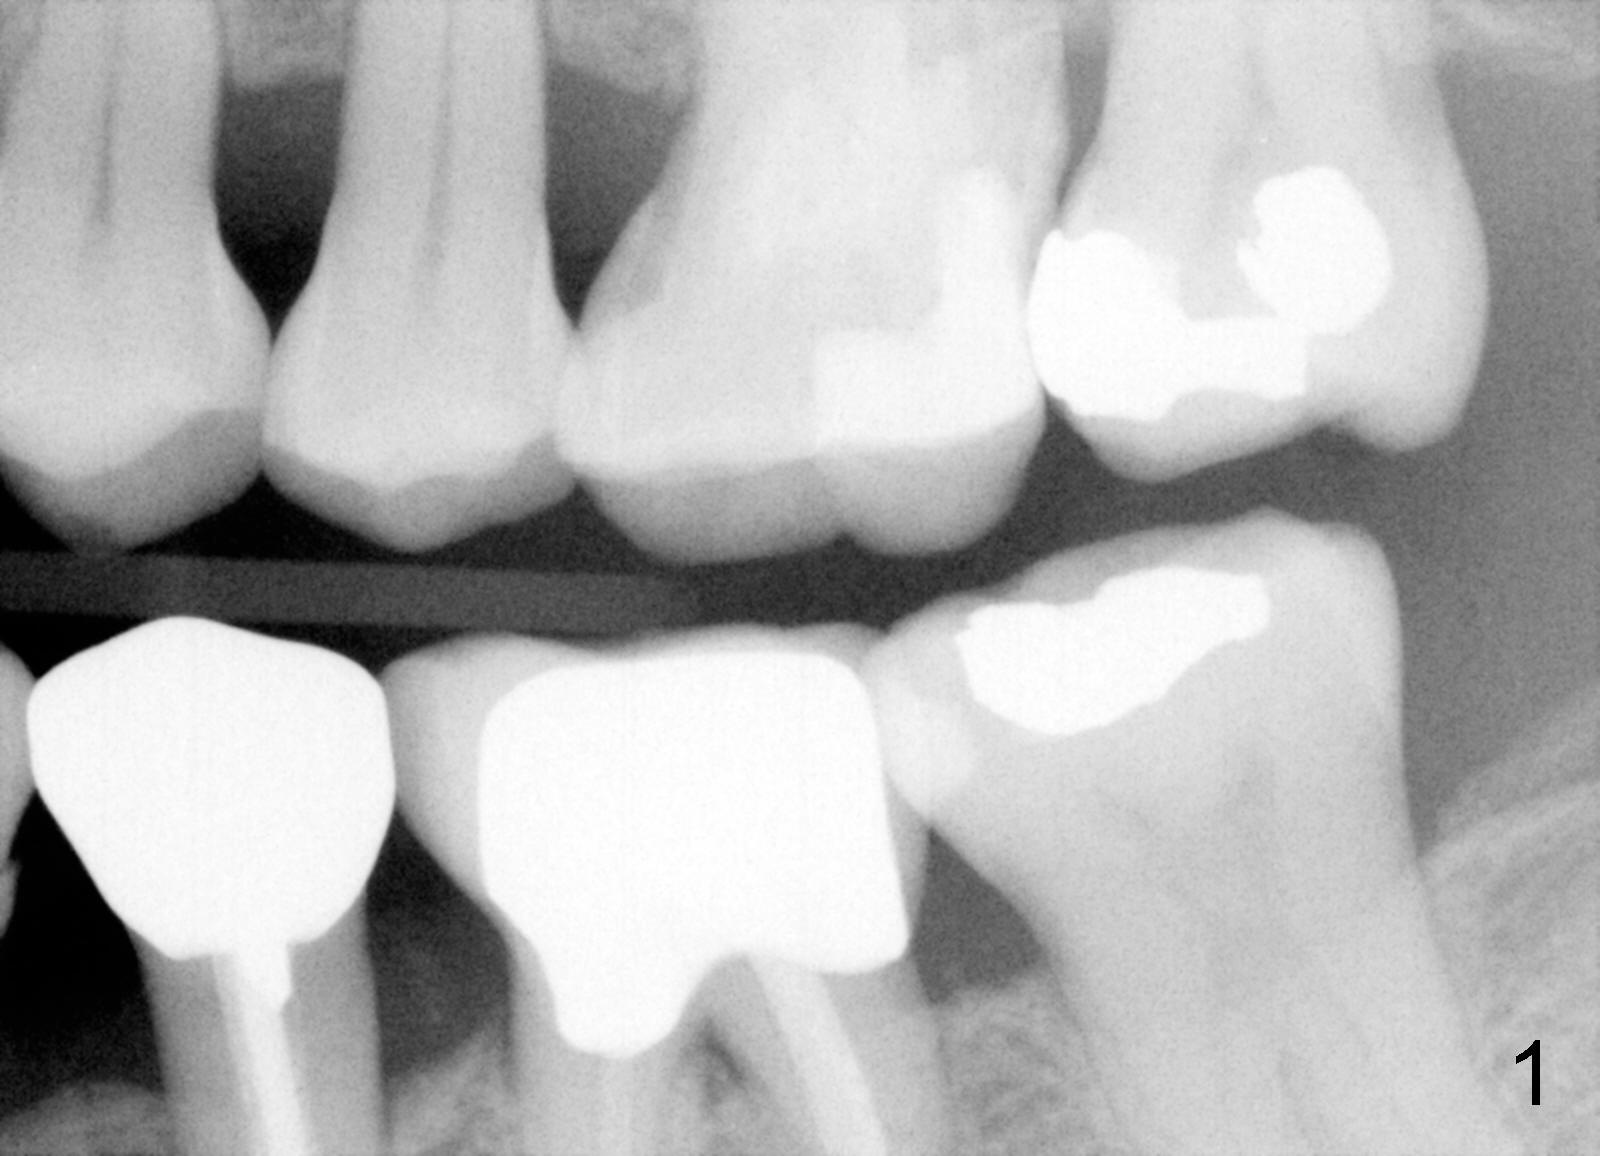

Bitewing and PAs for Upper Left Quadrant

X-ray was taken on 01/18/2010 (Fig.1) and 06/11/2011 (Fig.2-4). Clinically there is no gross lesion in the upper left quadrant, although pain is vague in position, according to the patient.